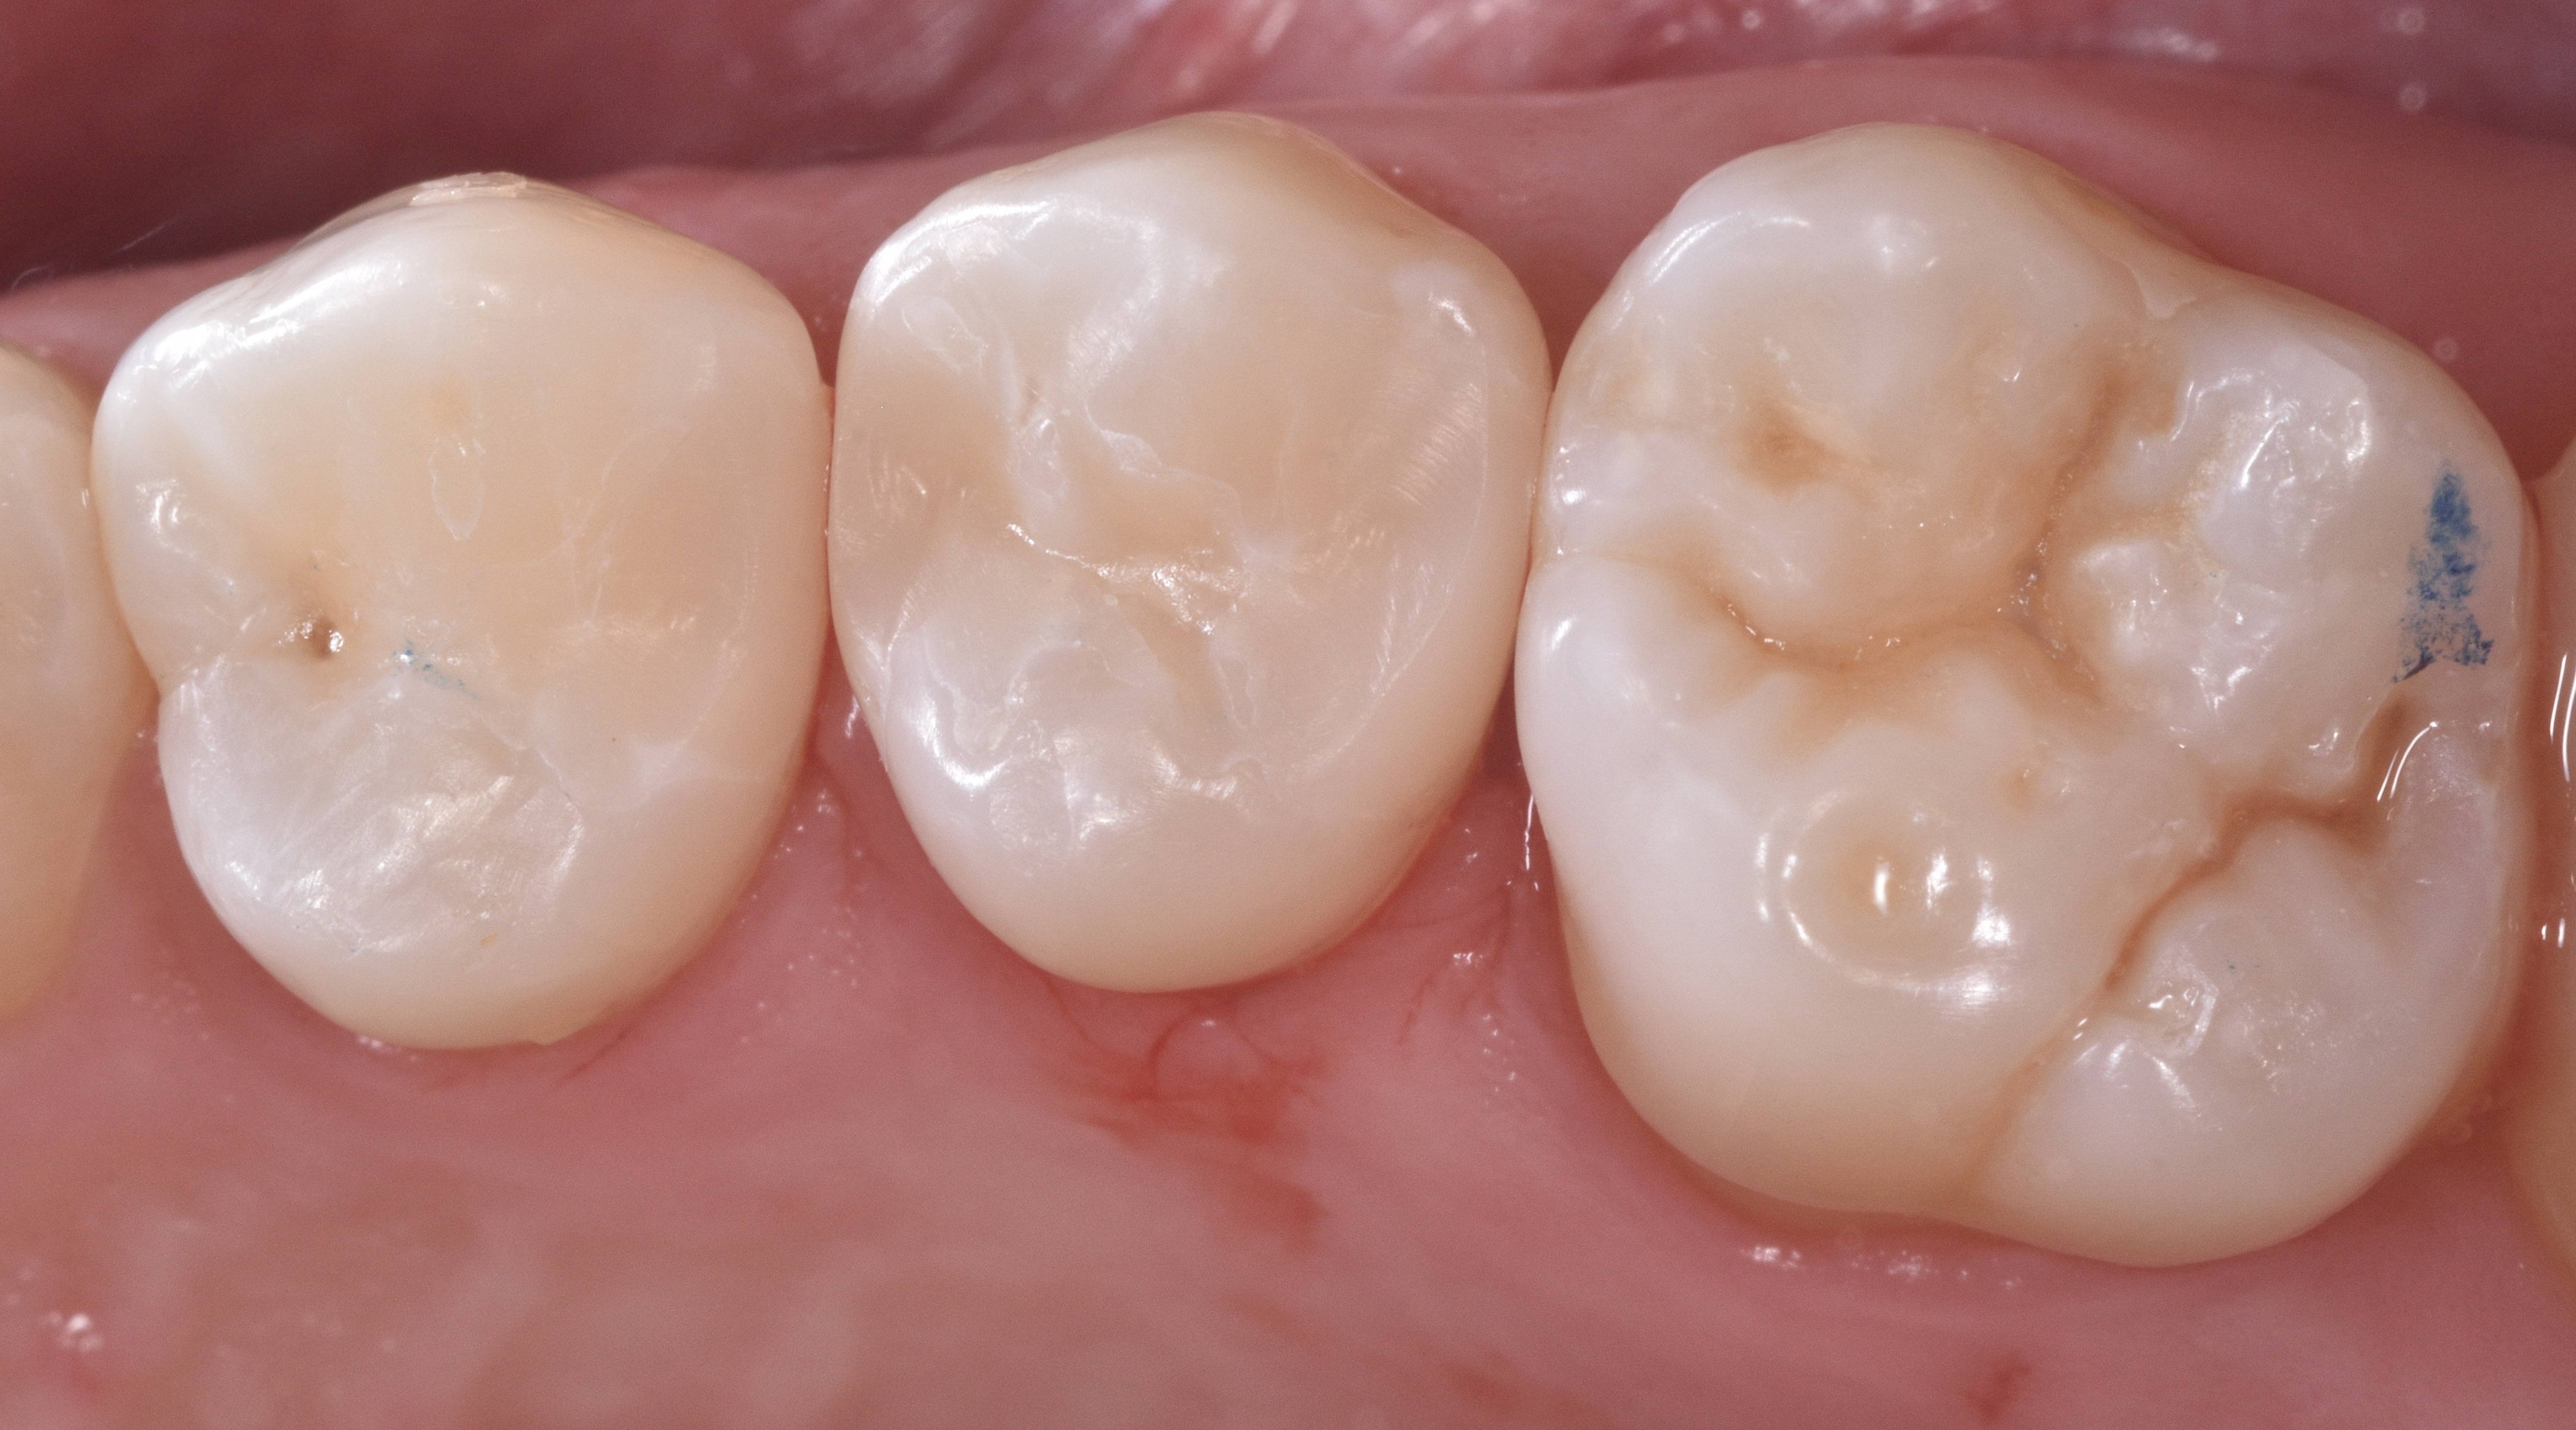

A 34-year-old female patient in good general health presented to my practice with interproximal carious lesions affecting teeth #12 on the distal-occlusal (DO) surface and #13 on the mesial-occlusal-distal (MOD) surface.

After profound anesthesia was accomplished using a carpule of OraBloc Articaine 4% with epinephrine 1:100.000 via infiltration, rubber dam isolation was completed (Black Hysolate-Coltene) (Figure 1)